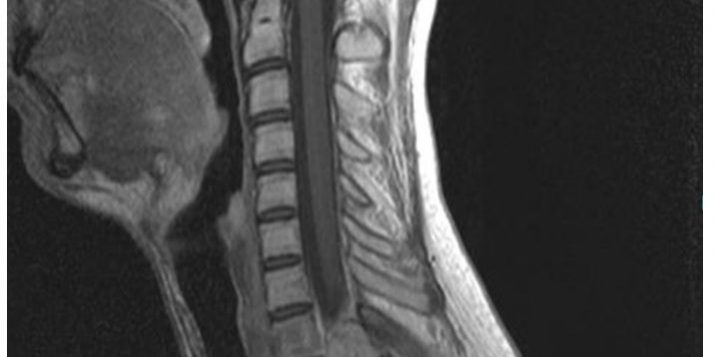

Ασθενής άδρας 28 ετών με πόνο στον αυχένα και τη ράχη καθώς επίσης και προοδευτική αδυναμία κάτω άκρων (δε>>αρ)

Ο απεικονιστικός έλεγχος έλεγχος με μαγνητική και αξονική τομογραφία της αυχενικής μοίρας της σπονδυλικής στήλης ανέδειξε χωροκατακτητική εξεργασία στο ύψος του Θ1-Θ2 σπονδύλου